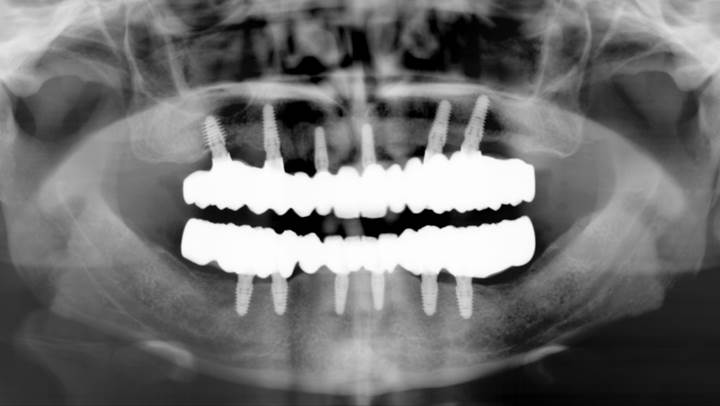

Clinical case: Full-mouth implants for mandibular & maxilla - restored using mixed prostheses

- Courtesy of Dr. Hyun Jun Kim, Korea -

Keywords

AnyRidge, full-mouth implants, mandibular, maxilla, edentulous, full mouth rehabilitation, Octa abutment, long-term clinical case, biological stability, Dr. Hyung Jun Kim

Products:

AnyRidge implant system